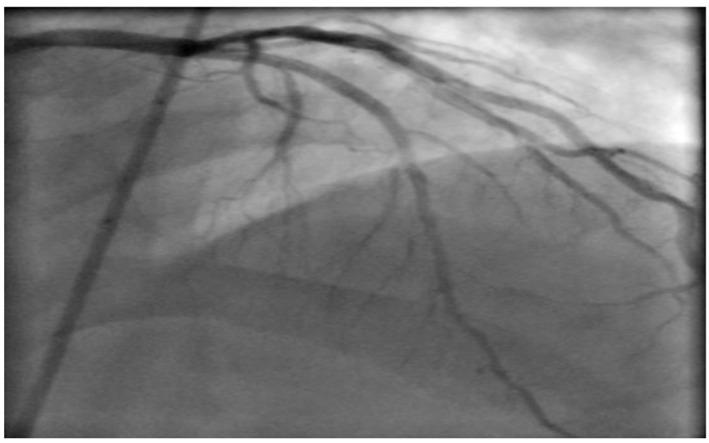

Although most of the patients presenting with ischemic heart disease have chest pains, there are other rare presenting symptoms like cardiac cephalgia. In this report, we present a case of acute coronary syndrome with an only presentation of exertional headache. It was postulated as acute presentation of coronary artery disease, due to previous history of similar presentation associated with some chest pains with previous left coronary artery stenting. We present an unusual case with cardiac cephalgia in a young patient under the age of 50 which was not reported at that age before. There are four suggested mechanisms for this cardiac presentation.

虽然大多数缺血性心脏病患者会出现胸痛,但也有其他罕见的症状,如心源性头痛。在本报告中,我们介绍了一例急性冠状动脉综合征,其唯一表现为劳力性头痛。由于既往有类似表现且伴有胸痛,曾行左冠状动脉支架置入术,故推测为冠状动脉疾病的急性表现。我们报告了一例50岁以下年轻患者的心源性头痛的罕见病例,此前该年龄段未见报道。关于这种心脏表现有四种推测机制。